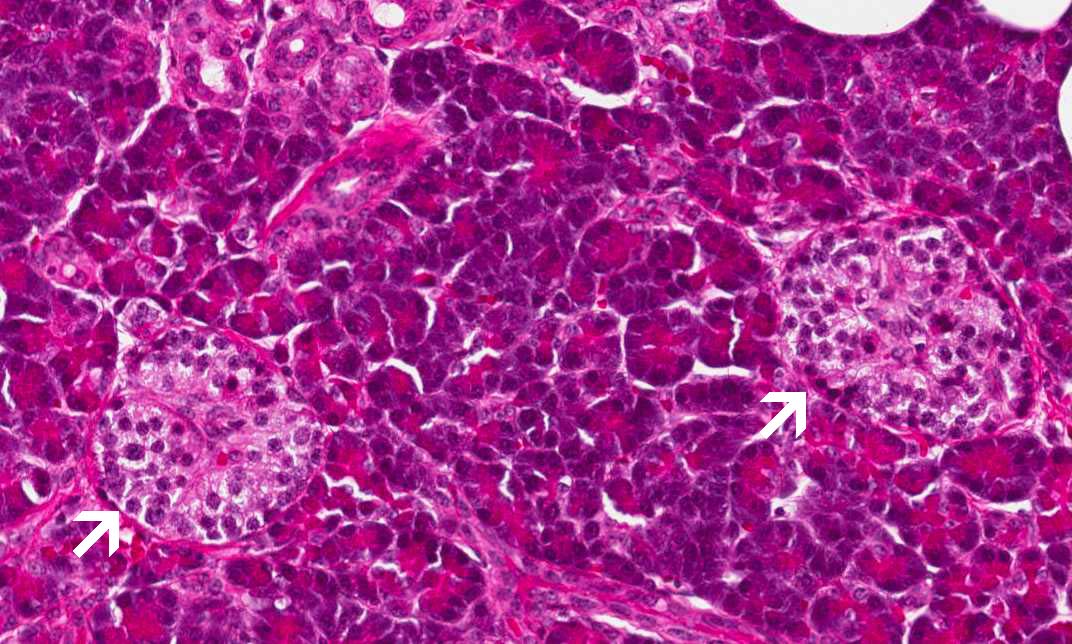

Area 1: Both exocrine and endocrine components are illustrated here. The islets of Langerhans are outlined by the arrows.

• The is obtained from a pancreas. There are lobules of acini separated by thin fibrous septa. Within these acini are islets of Langerhans (arrow) (Area 1). Pancreatic ducts lined by columnar epithelium are also present (Area 2).